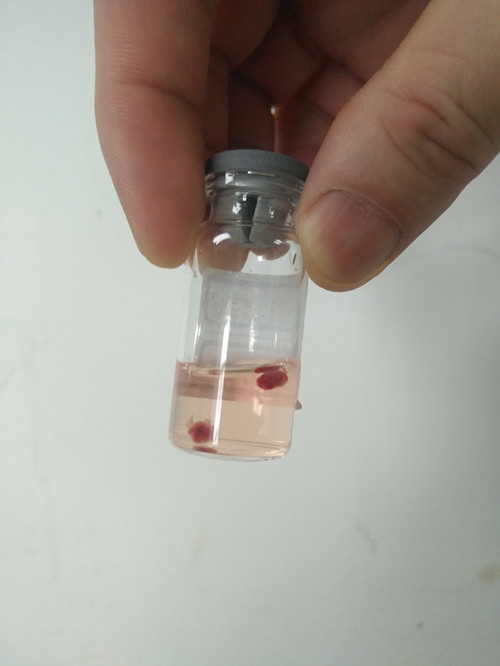

经冷冻活检获得的肺组织

近日,我院呼吸与危重症医学科杨拴盈主任、张德信副教授成功给1例弥漫性肺疾病患者行TBCB检查,取材过程顺利,取材量充足。文献检索提示,该患者是西北地区首例应用TBCB技术成功获得组织学标本的病例。该项技术在我院的成功开展使得我院呼吸与危重症医学科对弥漫性肺疾病的诊断更精准、更微创、费用更低,同时进一步促进我院呼吸介入病学的发展,为更多弥漫性肺疾病患者的诊治创造条件。